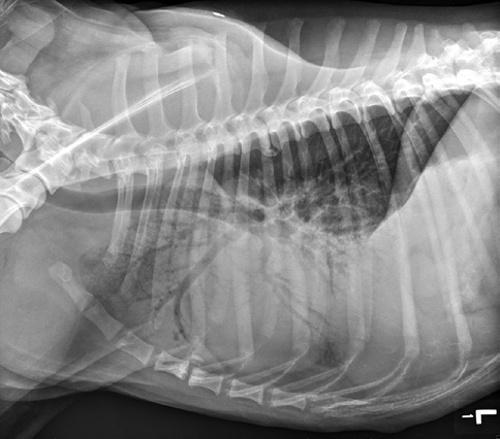

Figure 1.2 Lateral thoracic radiograph showing cranioventral pulmonary infiltrates creating an alveolar pattern consistent with aspiration pneumonia.

depression, pale mucous membranes, dyspnea, crackles or increased bronchovesicular lung sounds, or decreased lung sounds ventrally (pleural effusion) or dorsally (pneumothorax), and cyanosis. Patients with diaphragmatic hernia may have decreased lung sounds dorsally or ventrally. Cyanosis is only seen with severe hypoxemia (at least 5 g/dl of deoxygenated hemoglobin), and thus the absence of cyanosis absolutely does not rule out hypoxemia. In anemic animals, cyanosis is unlikely to be detected due to decreased hemoglobin concentration, and therefore should not be relied upon to diagnose hypoxemia [8].

Thoracic radiographs may show pulmonary parenchymal infiltrates ventrally consistent with pneumonia, caudodorsally consistent with non- cardiogenic pulmonary edema, and in the perihilar region consistent with congestive heart failure. In the trauma patient,

pulmonary contusions, which can be present in any lung field(s), may not become radiographically apparent for up to 48 hours, although peak opacification has been shown to occur at 6 hours in human trauma patients [10].